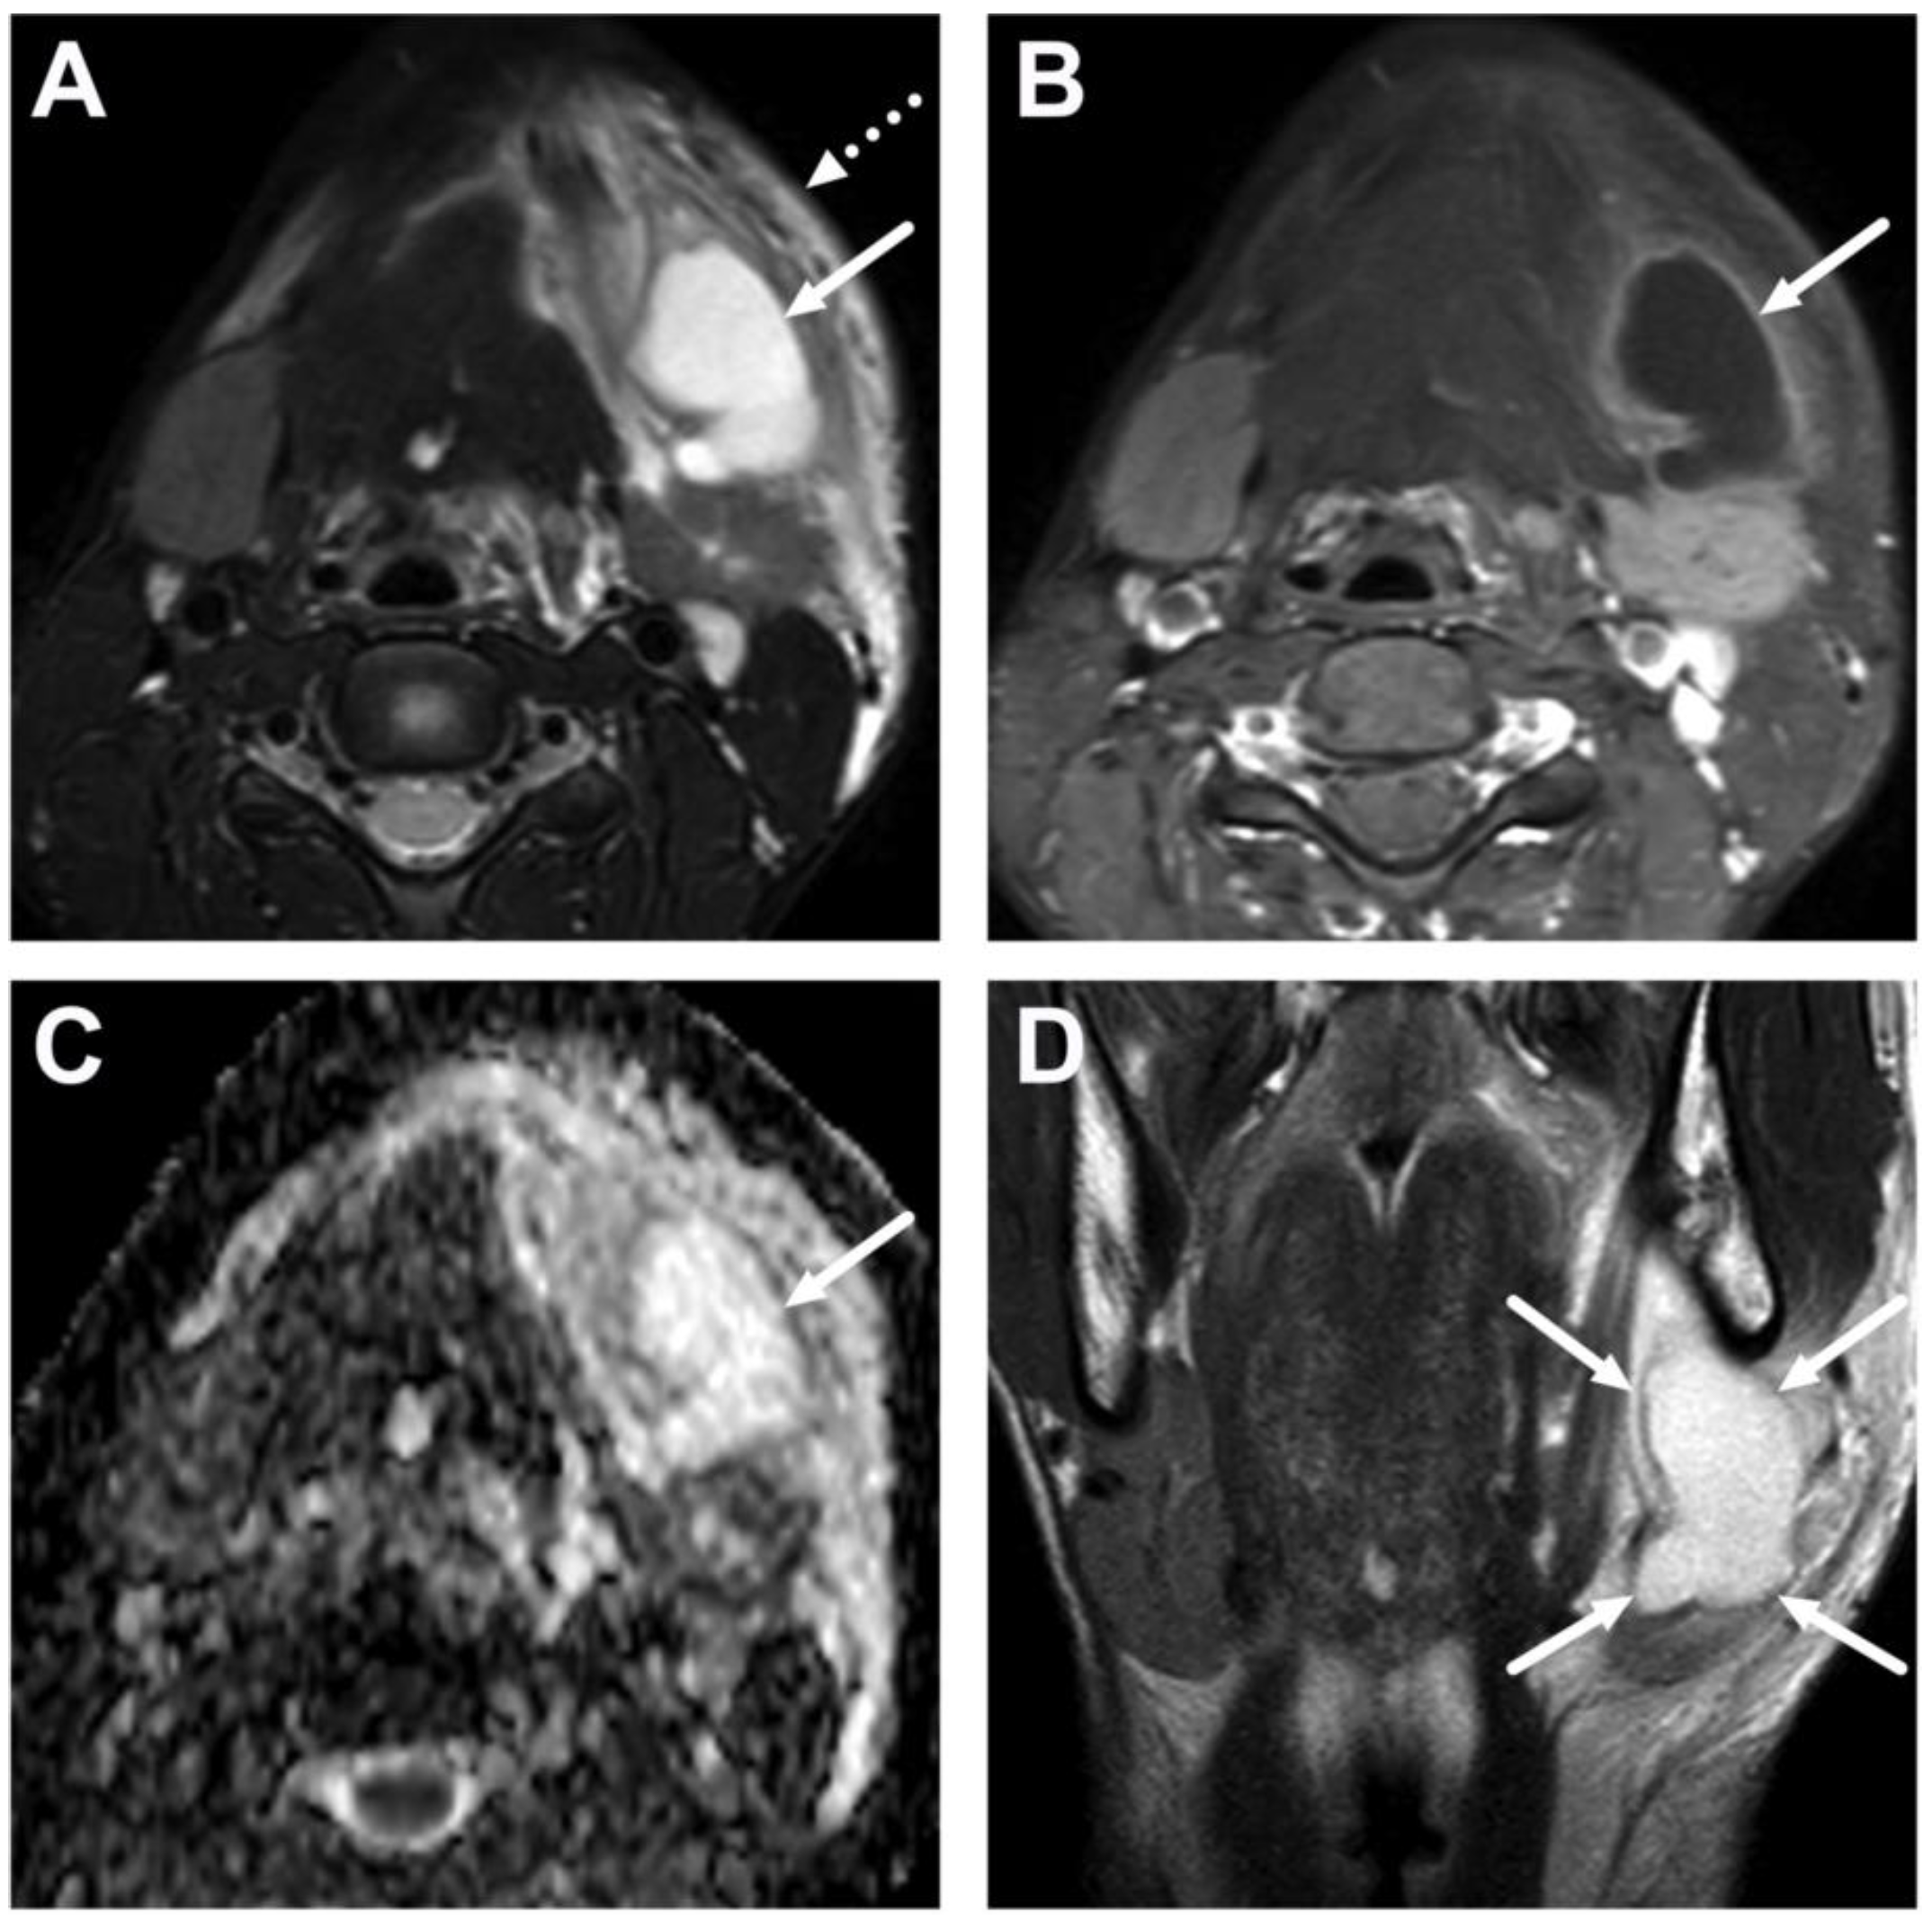

6.2. Venous Thrombosis

| Complications | Whole protocol | Abscess extending to multiple deep neck spaces, mediastinis, venous thrombosis, and airway compromise. | Detection of potentially life-threatening conditions. | Magnetic resonance angiography (MRA) or CECT may be needed to diagnose venous thrombosis; defining airway compromise is difficult. |